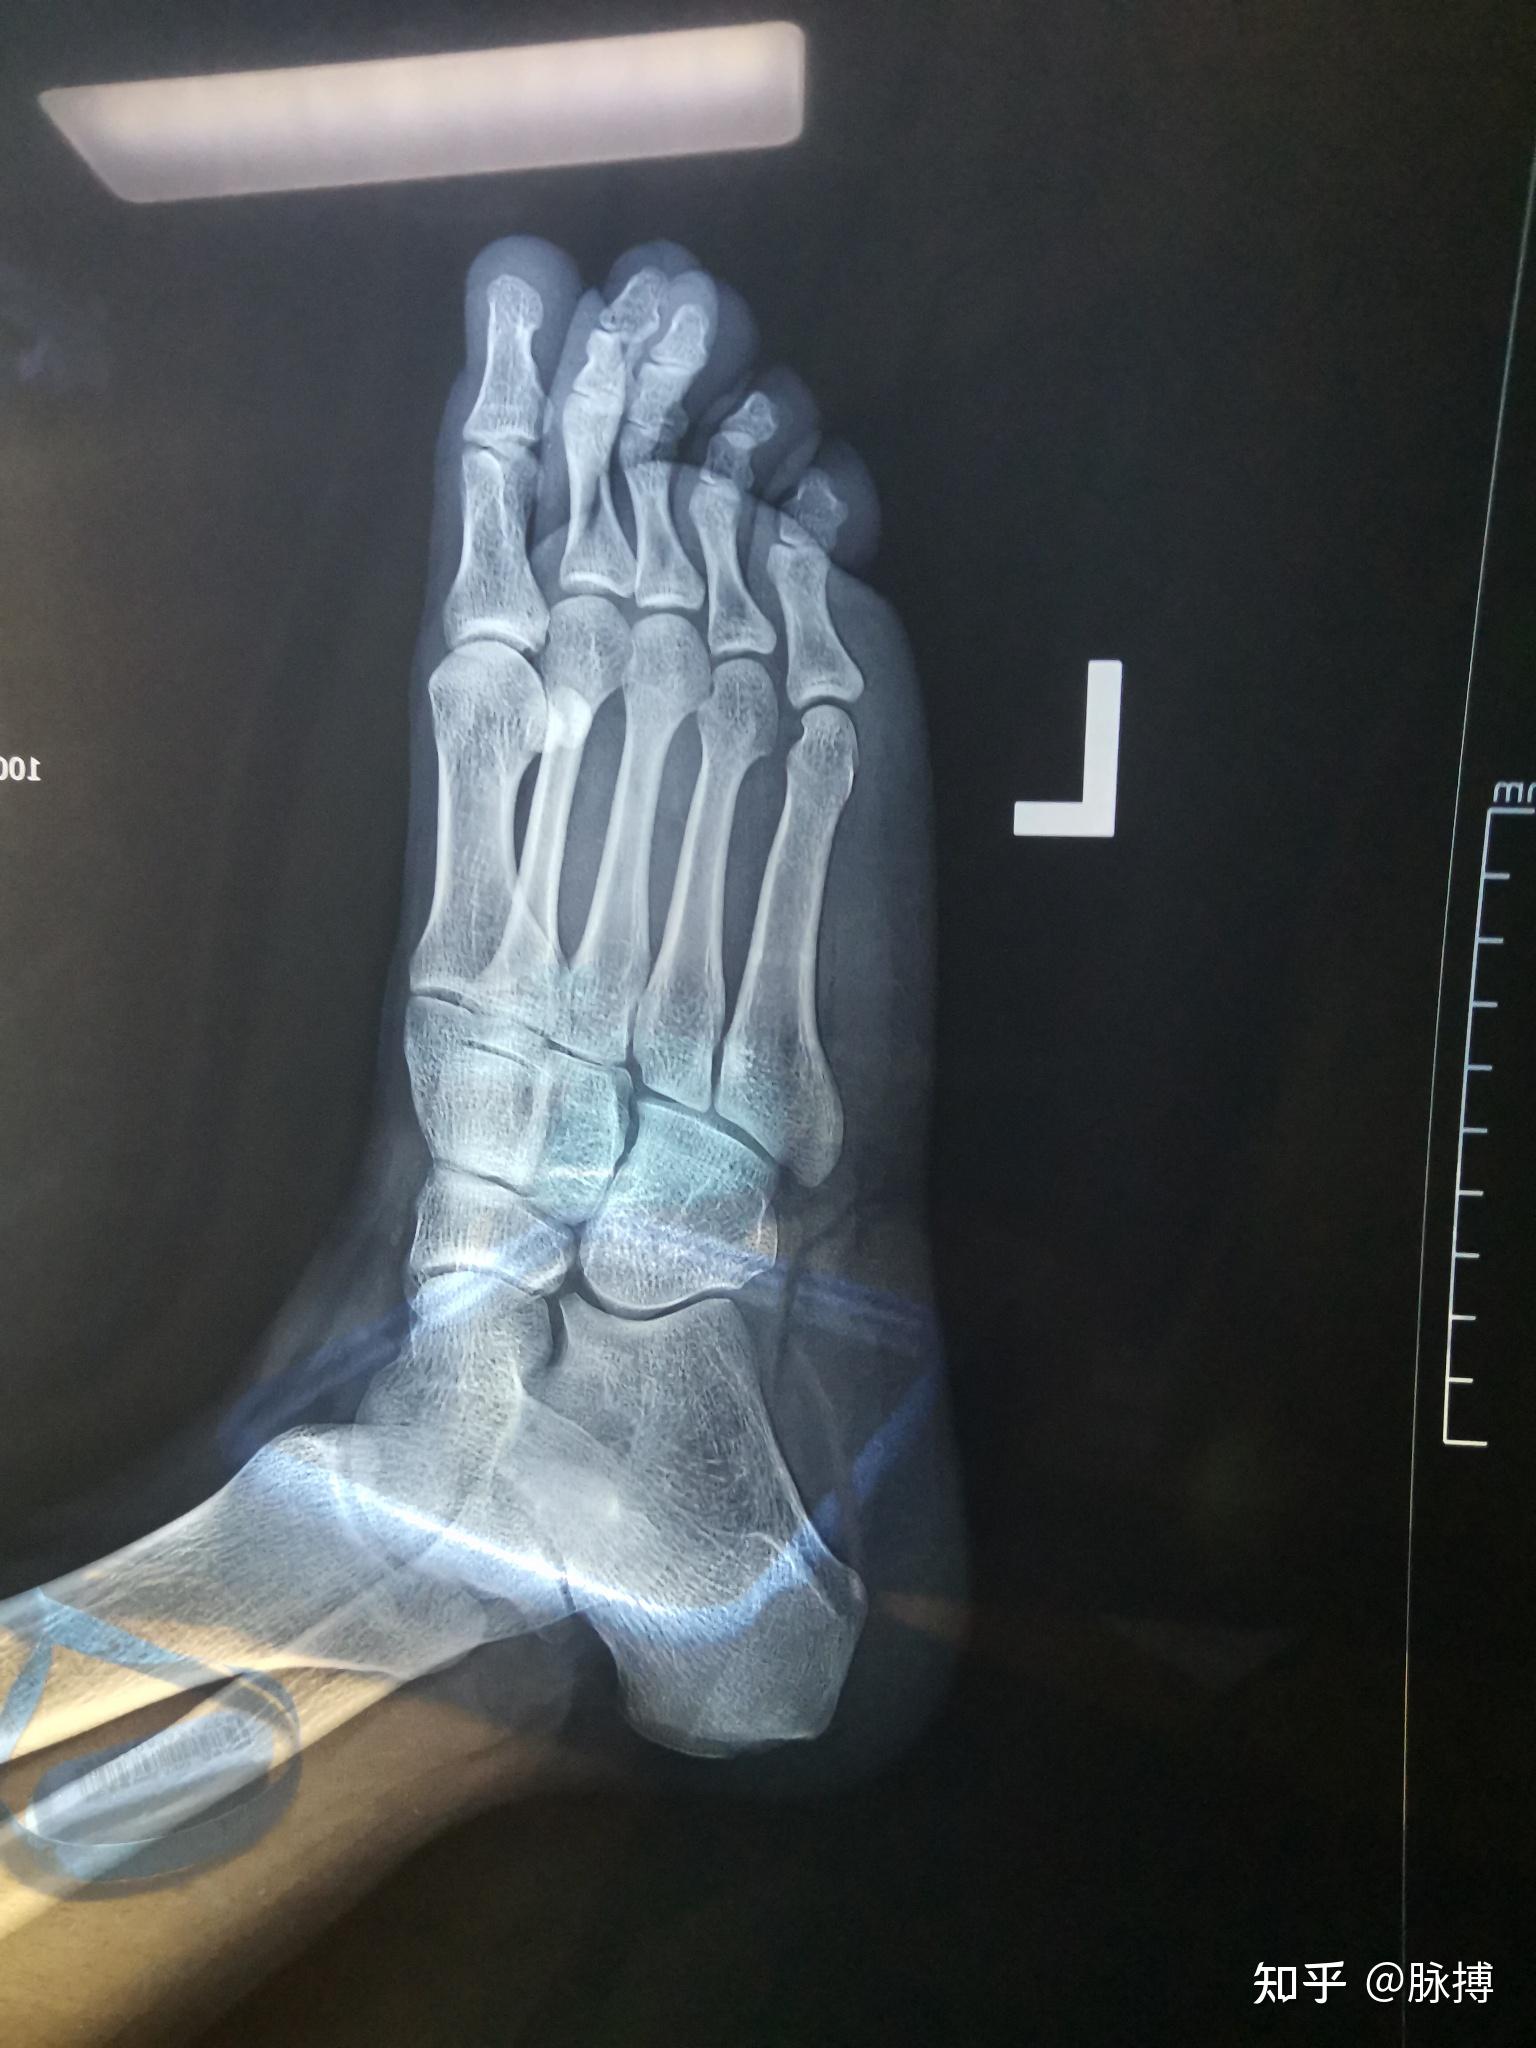

外翻扭伤,肿的一般,拍片看大夫说骨折,没说具体情况,请大夫给看看